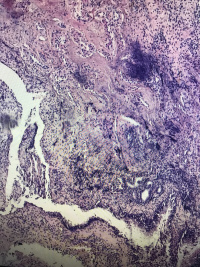

鼻息肉

性别

女

年龄

27

临床诊断

一般病史

鼻窦炎

标本名称

大体所见

灰白碎组织,大小3.2✖️2.4✖️0.5cm,部分成囊状

鼻粘膜息肉。